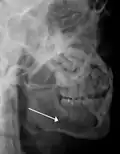

Rigid internal fixation of parasymphysis fracture of the mandible. White arrow marks fracture, black arrow marks arch bar on lower teeth -